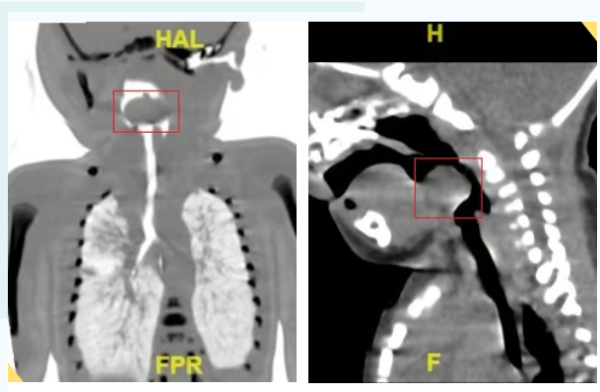

齐鲁晚报·齐鲁壹点 姜曼配资官方网站 近日,临沂市妇幼保健院收治了一名会厌囊肿的新生儿。患儿出生两天因呼吸困难转入该院,CT显示在会厌上方有一个23×17×11....